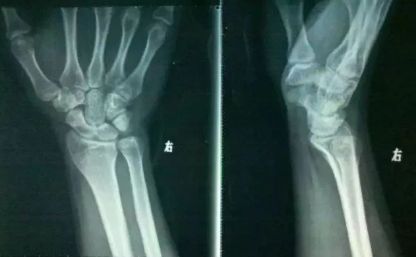

4、常见的“弹响”

下面是一些常见的发生弹响的关节: